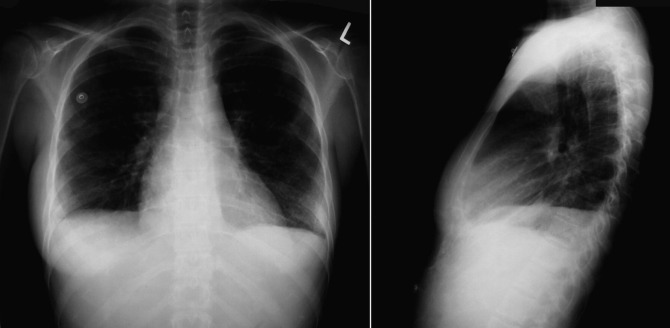

In constrictive pericarditis ( Graphic 16-1 ; Figs. 16-16 to 16-23 ) , the CPS is usually nonspecifically and mildly enlarged. Occasionally, the heart is normal or small in size. The left atrium is the most frequently enlarged chamber, because its enlargement is less restricted by pericardium. The right atrial contour on the frontal chest radiograph may be flattened. Calcification of the pericardium suggests past tuberculosis, but since tuberculosis has become uncommon at most centers, 90% of cases of constrictive pericarditis are currently noncalcified. Calcification, especially diaphragmatic, is not specific for constrictive physiology; it may be seen in the absence of cardiac compression. The apical surface is less frequently calcified than the interventricular and atrioventricular grooves. The apex seldom calcifies prominently in constrictive pericarditis; this finding suggests a calcified apical aneurysm rather that constrictive pericarditis.